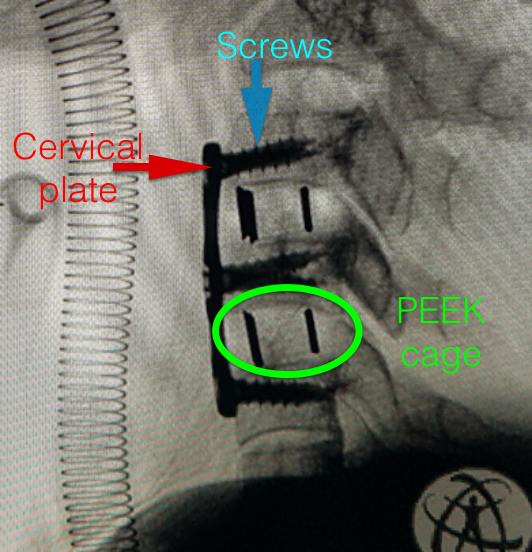

After the decompression/discectomy, the surgeon proceeds to fusion part of surgery. In the emptied disc space, a bone graft or a cage is placed to maintain the height of the disc space and to promote bone formation between the two vertebra. Nowadays, most surgeons prefer putting PEEK(Polyethyletherketone) cages in the disc spaces. Over this cage a titanium plate is put across the upper and lower vertebral body to prevent any movement between them.

Delayed complications, that present after months may be due to loosening of implants(Plate and screws) or extrusion of graft (either bone or PEEK cage) from the disc space. This may lead to increasing pain in the neck and may need revision surgery.